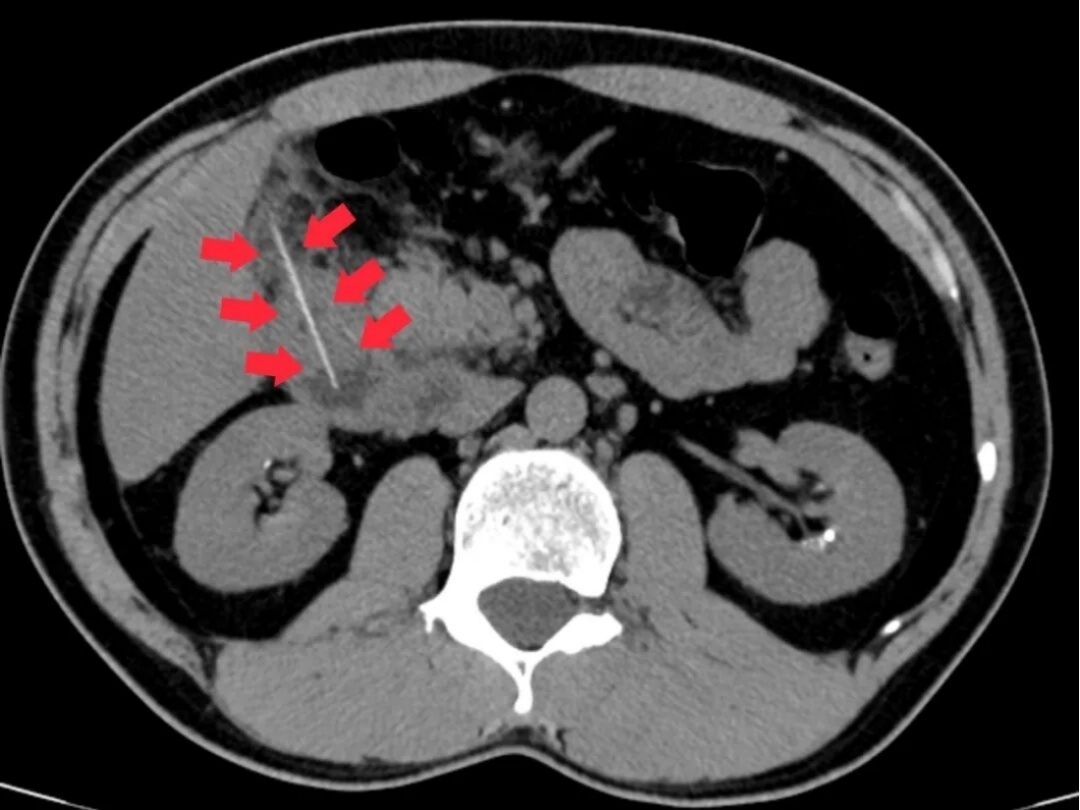

急诊科医生立即为其安排腹部CT检查,结果发现一根牙签滞留于十二指肠降部,且尖端已刺穿肠管壁,引发了局限性腹膜炎。情况危急,若任由发展,可能导致感染扩散、休克甚至危及生命。陈先生随即以“消化道异物并穿孔”被收治入院。

图示箭头处为异物牙签。通讯员供图

外科团队火速完成术前检查,科主任麦伟锦组织多学科会诊,分析CT影像后发现,穿孔处已形成局部粘连,取出时需控制牵拉力度,决定采取“消化内镜优先、手术兜底”的双保险方案。李伟杰医师在病床前,用影像直观讲解治疗思路,消除了患者的疑虑。